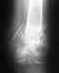

Здравствуйте! Моя мама (51 год) в декабре сломала голеностоп, ей предложили поставить пластину вместо гипса.

Операцию делалаи по месту жительства мамы в Челябинской области. 3 месяца она была на больничном, сейчас уже работает, но отек на ноге так и не спал(( Мама хочет в августе уже снять пластину, но уже не доверяет своим врачам, можно узнать возможно ли сделать подобную операцию в вашем институте и сколько это будет стоить? Очень жду ответа. Спасибо огромное.С уважением,Толкачева Инна

Можно. Положим бесплатно. Пришлите на alex61(собака)gmail.com рентгенограммы с кратким описанием ситуации или со ссылкой на это сообщение.